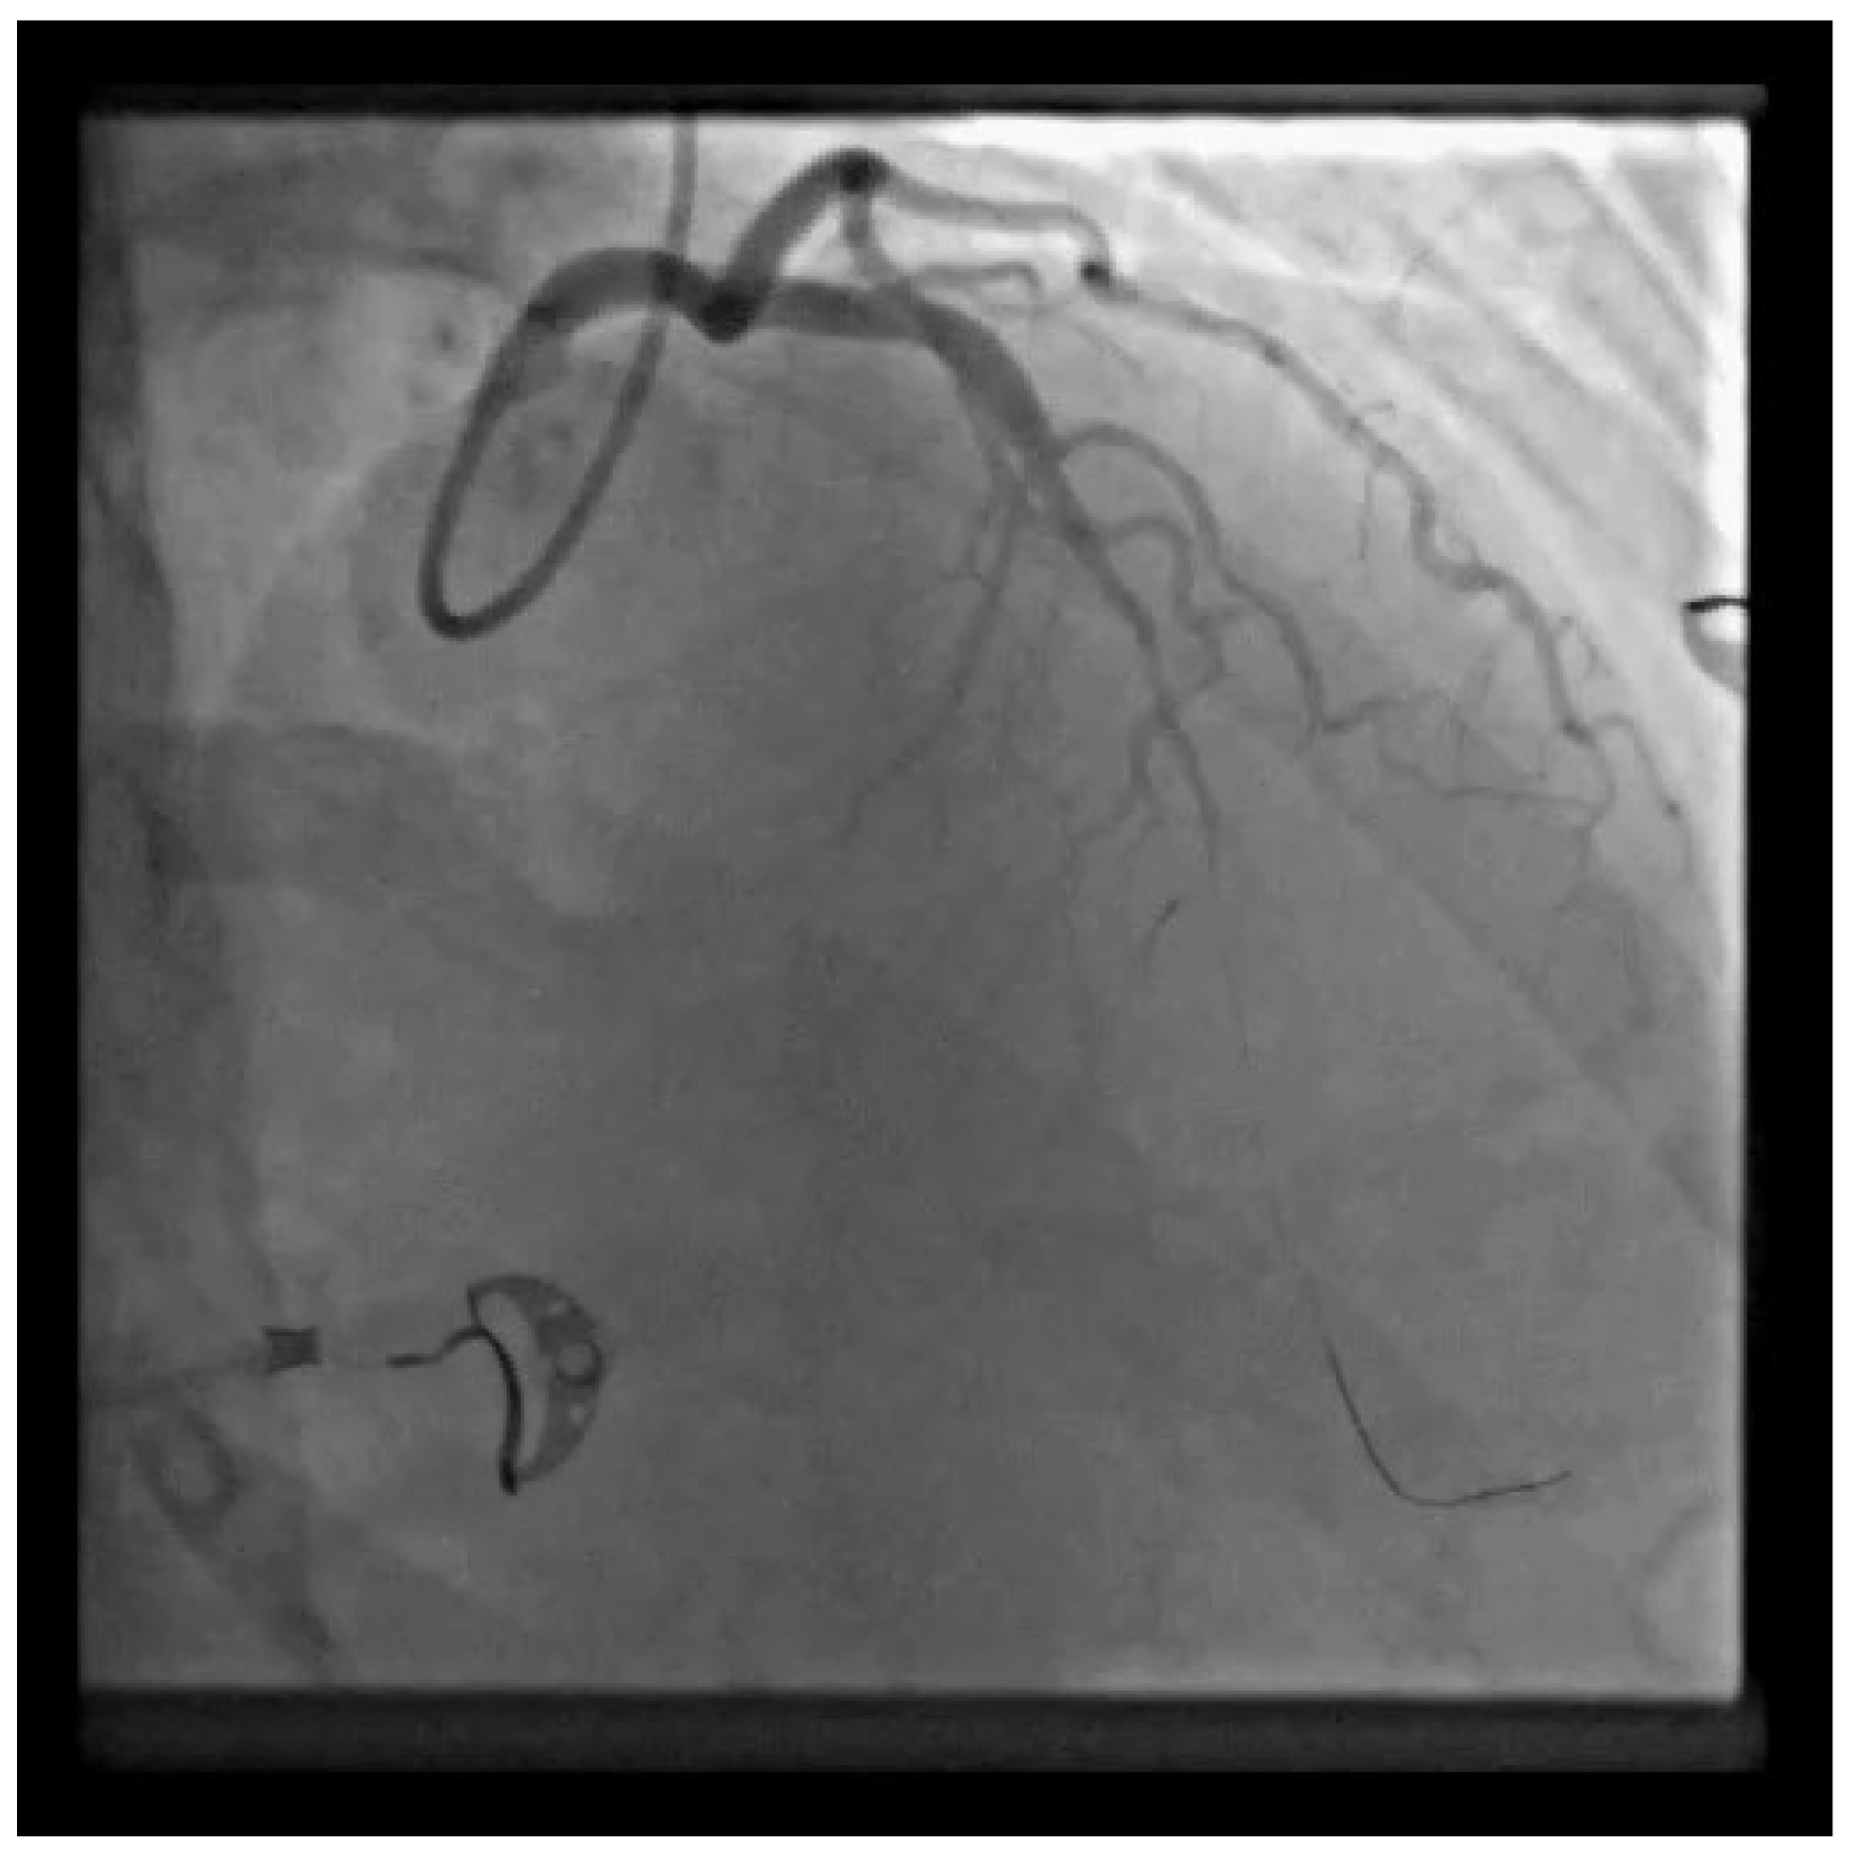

LAD SCAD from the medial to distal segment was observed along with lumen occlusion of the coronary artery; it was SCAD type 4. After the guide insertion, LAD was wired and dilated with balloon inflation (1.5 × 15 on 4 atm) (Video S2).